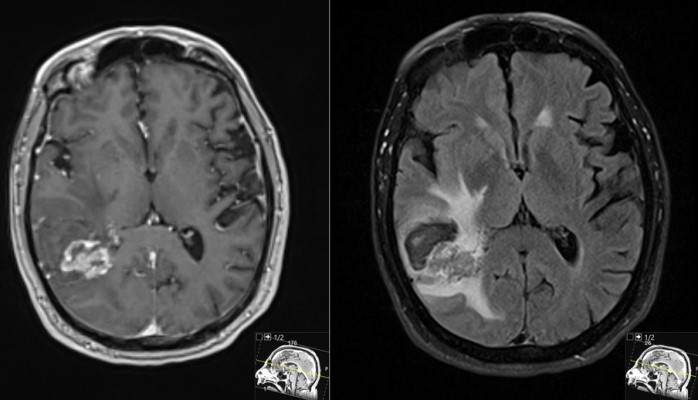

This is a 69 year old male with a known history of renal cell carcinoma who presented with cognitive decline and a neck mass.He had memory issues which were attributed to chemotherapy. He also was having new headaches. The neck mass was due to an infection. Neurologic examination was relatively unremarkable.

- Pre-Op